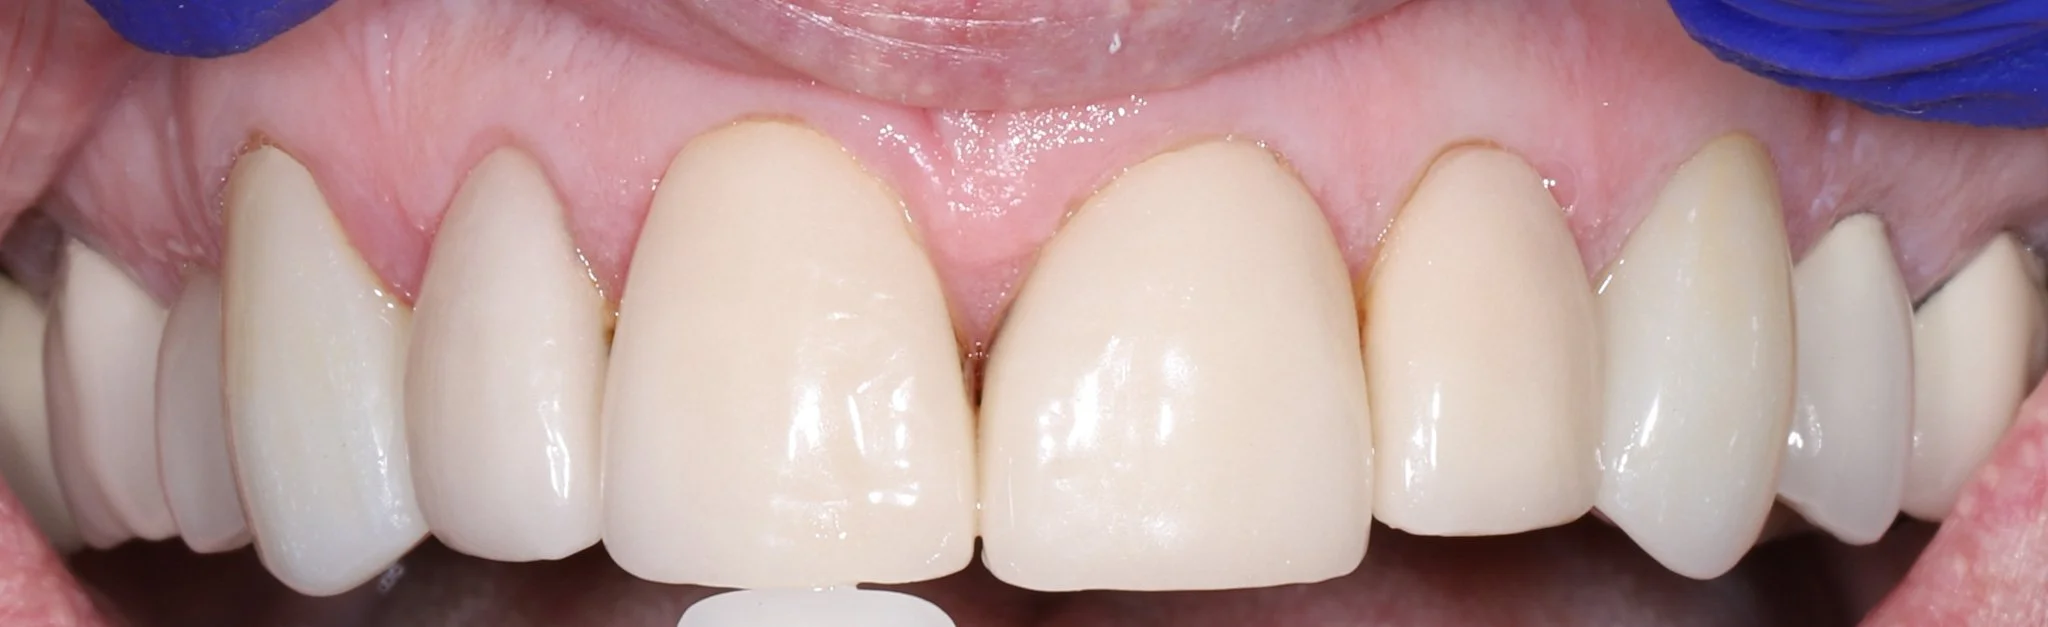

Close-up of a person's upper front teeth, showing straight, white teeth with healthy gums with ideal aesthetics.  These teeth were restored with porcelain crowns.

After: Protected teeth with proper aesthetics and function